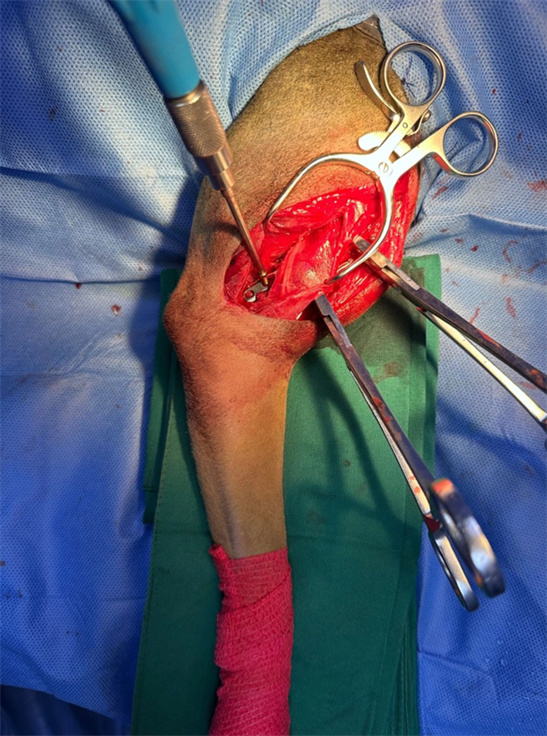

右肱骨幹橫形骨折採外側入路,全開放性接觸固定頭側及外側雙 骨板.橫向骨折板孔用頭側接骨板上的加壓螺絲縮小。

由於是PRCL鎖定接骨板系統,力求接骨板塑形完美,但不要刻意追求塑形絕對完美